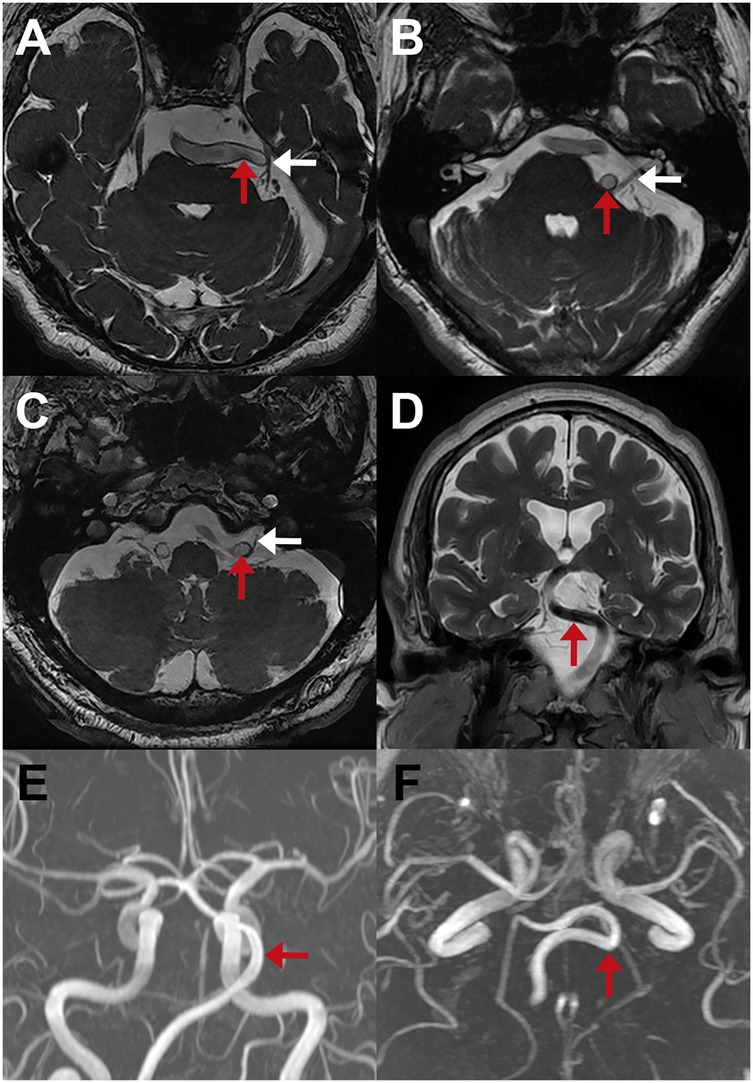

Reports from external neuroradiologists using high-resolution MRI sequences (3D-FIESTA or 3D-CCIS) showed concordance with intraoperative identification of VBD in 43 patients (63.2%) (Table 2). However, when imaging was reviewed by our neuroradiologists, VBD was identified in all cases. Representative MRIs are shown in Figure 6 for TN (Figure 6A), HFS (Figure 6B), and GPN (Figure 6C). In a subset of patients, DSA or MRA was also performed (Figures 6E,F), providing valuable information on VBA tortuosity and course, which aided in preoperative planning and selection of the appropriate decompression strategy.

MRI scans show various brain cross-sections. Panels A, B, C, and D highlight intracranial structures with red and white arrows indicating cranial nerves and course of the VBA. Panels E and F display blood vessels with red arrows pointing to the dolichoectatic course of the VBA.

Figure 6. Preoperative neuroimaging findings in patients with cranial nerve compression due to VBD. (A–C) MRI 3D-FIESTA sequences showing compression of the CN V (A), CN VII (B), and CN IX (C) by the VBA (red arrows); corresponding nerves are indicated with white arrows. (D) Coronal MRI suggesting displacement of the brainstem by the VBA (red arrow). (E,F) Axial and coronal MR angiography demonstrating the tortuous course of the VBA (red arrows).